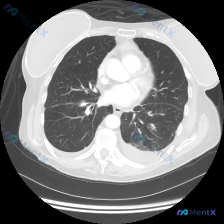

胸部影像病例:双肺下叶阴影+双侧胸腔积液,这个组合最可能是什么原因?

最近整理了一份胸部CT肺窗横断面图像的分析,给大家分享一下。

病例基本情况(影像学):

- 双肺整体透亮度基本对称

- 右肺下叶及左肺下叶后基底段可见区域性磨玻璃样改变

- 双侧胸膜下可见新月形、均一的高密度影,贴附于后胸壁,边缘较平直(胸腔积液)

- 双肺肺门区肺纹理走行正常,气管及主支气管开口无明显狭窄或扩张

- 心影形态正常,纵隔居中

刚看到这个影像时,第一印象是双肺下叶的磨玻璃影和双侧胸腔积液。这个组合其实有几个关键鉴别方向:

心源性水肿(心力衰竭)

- 支持点:双侧胸腔积液、双肺下叶背侧重力依赖区磨玻璃影(典型的心肺水肿分布),心影形态正常(可能是射血分数保留的心力衰竭)

- 反对点:没有提供心功能不全的病史,但影像学表现很典型

炎性渗出(肺炎/非典型肺炎)

- 支持点:磨玻璃影可能是炎性渗出

- 反对点:胸腔积液为双侧对称性,且磨玻璃影分布于重力依赖区,不符合典型肺炎的叶段分布

全身性疾病(低蛋白血症/肾功能不全)

- 支持点:低蛋白血症或肾功能不全可导致胸腔积液和肺水肿

- 反对点:没有肝肾功能异常的病史,心影形态无明显扩大

这个影像的核心是“双侧胸腔积液+双肺背侧磨玻璃影”的组合,按照临床思维的“模式识别”和“一元论”原则,心源性水肿是最常见、最符合的病因。虽然没有提供病史,但影像学表现已经非常典型,需要进一步结合BNP、心脏超声等检查明确。